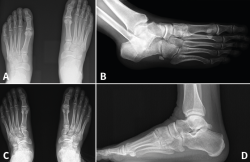

Figura 4. Caso 2. Radiografías lateral y anteroposterior sin carga de control tras la cirugía con fijación no rígida.

Se realiza cirugía con 2 suturas intraóseas C1-M2 y C2-M1 mediante la técnica descrita anteriormente (Figura 4). Se siguió un protocolo posquirúrgico igual al del caso anterior: revisión de la herida a los 10 días, descarga hasta las 6 semanas, carga parcial hasta las 8 semanas con bota y comenzar la carga completa con calzado cómodo con plantilla con soporte de arco longitudinal interno hasta un año postoperatorio.